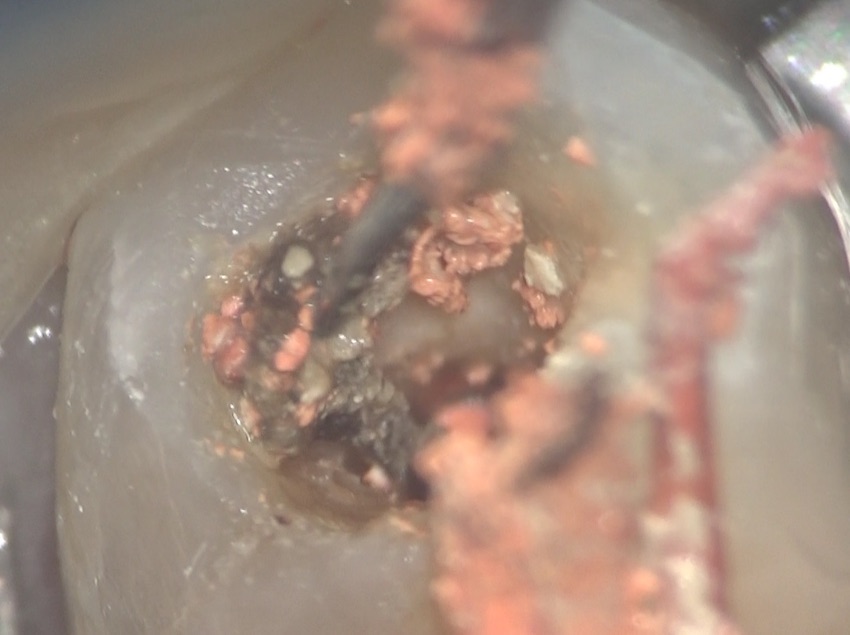

マイクロエキスかと呼ばれる耳かきのような器材で汚れを取り除くと、

内部から、ドス黒い軟組織が出てきました。

こんなものが入っていました。恐ろしいですね。

こんなに汚れていては、今後問題が起きても不思議はないですね。このようなケースがあるので、被せ物をする予定の歯に、以前に根管治療が施されいる場合は、再根管治療を行うことをすすめるのです。